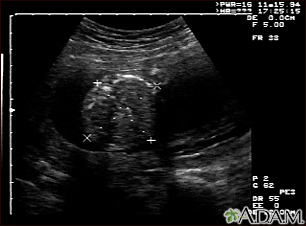

BACK TOTOP Browse A-ZSearchBrowse A-ZABCDEFGHIJKLMNOPQRSTUVWXYZ0-9 Ultrasound, normal fetus - abdomen measurementsBackUltrasound, normal fetus - abdomen measurementsThis is a normal fetal ultrasound performed at 19 weeks gestation. Many health care providers like to have fetal measurements to verify the size of the fetus and to look for any abnormalities. This ultrasound is of an abdominal measurement. It shows a cross-section of the abdomen, and the measurements are indicated by the cross hairs and dotted lines. E-mail FormEmail ResultsName:Email address:Recipients Name:Recipients address:Message: Review Date: 10/15/2024 Reviewed By: John D. Jacobson, MD, Professor Emeritus, Department of Obstetrics and Gynecology, Loma Linda University School of Medicine, Loma Linda, CA. Also reviewed by David C. Dugdale, MD, Medical Director, Brenda Conaway, Editorial Director, and the A.D.A.M. Editorial team. The information provided herein should not be used during any medical emergency or for the diagnosis or treatment of any medical condition. A licensed medical professional should be consulted for diagnosis and treatment of any and all medical conditions. Links to other sites are provided for information only -- they do not constitute endorsements of those other sites. No warranty of any kind, either expressed or implied, is made as to the accuracy, reliability, timeliness, or correctness of any translations made by a third-party service of the information provided herein into any other language. © 1997- A.D.A.M., a business unit of Ebix, Inc. Any duplication or distribution of the information contained herein is strictly prohibited. © 1997- All rights reserved. A.D.A.M. content is best viewed in IE9 or above, Firefox and Google Chrome browser.Content is best viewed in IE9 or above, Firefox and Google Chrome browser.

Ultrasound, normal fetus - abdomen measurementsBackUltrasound, normal fetus - abdomen measurementsThis is a normal fetal ultrasound performed at 19 weeks gestation. Many health care providers like to have fetal measurements to verify the size of the fetus and to look for any abnormalities. This ultrasound is of an abdominal measurement. It shows a cross-section of the abdomen, and the measurements are indicated by the cross hairs and dotted lines. E-mail FormEmail ResultsName:Email address:Recipients Name:Recipients address:Message: